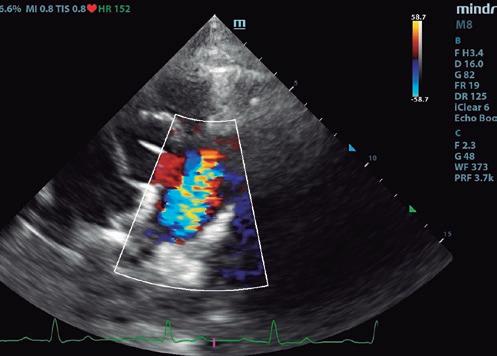

Boehringer Ingelheim España ha programado hasta final de año las Jornadas de Ecografía Avanzada patrocinadas por Vetmedin que recorrerán diversas ciudades del territorio nacional junto al referente Germán Santamarina. La finalidad de la iniciativa es brindar formación especializada y participativa a los especialistas en ecografía ambulante, un colectivo con necesidades muy específicas al cual Boehringer Ingelheim brinda su apoyo.

Las jornadas comenzaron en Barcelona y Alicante los días 21 y 22 de junio, respectivamente. Madrid, País Vasco y Andalucía y Canarias serán las siguientes durante las semanas del 23 de octubre y del 13 de noviembre. Todas las sesiones tienen una duración de medio día y se desarrollan en formato de mesa redonda a partir de las 15:00 h.

Con el objetivo de promover una experiencia más cercana e interactiva, las sesiones se organizan en grupos pequeños, con un límite de 10 a 15 participantes por sesión.